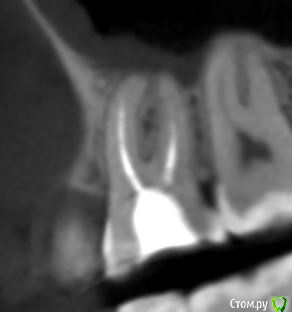

dmitrib81 Опубликовано 20 февраля, 2020 Автор Поделиться Опубликовано 20 февраля, 2020 еще фото Ссылка на комментарий

krokomot Опубликовано 19 февраля, 2020 Поделиться Опубликовано 19 февраля, 2020 в медиальном корне недопломбировка и наличие вероятно 4ого канала. Ссылка на комментарий

dmitrib81 Опубликовано 20 февраля, 2020 Автор Поделиться Опубликовано 20 февраля, 2020 Зуб делали много лет назад. Примерно неделю назад появились периодические боли, бывает целый день не болит, потом снова ноющая боль. С приёмом пищи никак не связано. На горячие и холод реакции нетПодскажите, может ещё прислать фоток из КТ Пикассо, а то я в этом ничего не понимаю, просто разных фото экрана прислал, без какого-либо понимания, на что смотреть.. Ссылка на комментарий